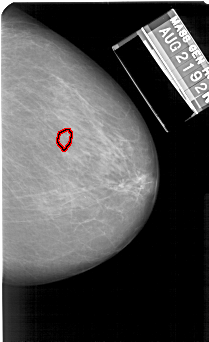

A_1131_1.RIGHT_MLO

RIGHT_MLO LINES 5491 PIXELS_PER_LINE 3661 BITS_PER_PIXEL 12 RESOLUTION 43.5 OVERLAY

FILE: A_1131_1.RIGHT_MLO.OVERLAY

TOTAL_ABNORMALITIES 1

ABNORMALITY 1

LESION_TYPE CALCIFICATION TYPE PUNCTATE DISTRIBUTION CLUSTERED

ASSESSMENT 4

SUBTLETY 3

PATHOLOGY MALIGNANT

TOTAL_OUTLINES 1